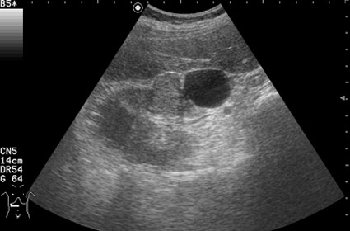

Поперечное серошкальное сканирование.

Обозначенный сегмент почки по структуре не отличим от рядом лежащих участков, выбухание контура над указанным сегментом тоже ни о чем не говорит, т.к. может быть просто дольчатостью.

Дольчатость почки в 56 лет?

При гистологии эта структура была почечно-клеточным раком (RCC).

В данном конкретном случае разница есть и она довольно существенная. Все-таки образование представленное на этой странице изо- или нормоэхогенное. В Вашем случае образование имеет повышенную эхогенность, примерно равную эхогенности окружающей почку клетчатки, что в пользу именно AML.